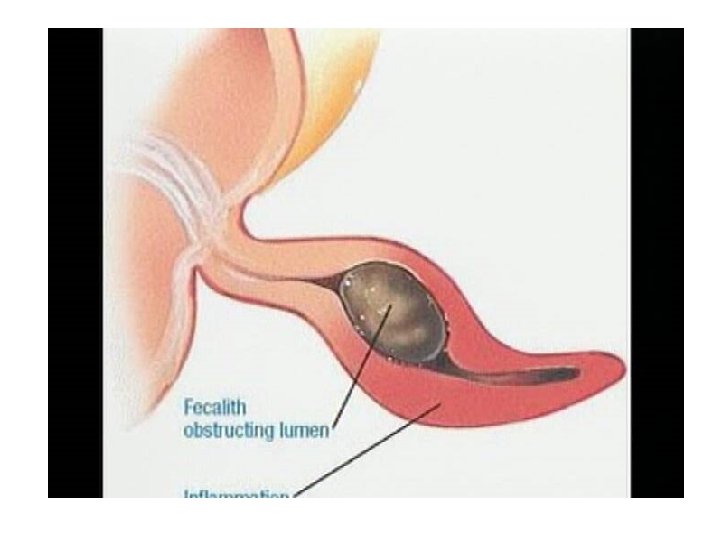

• Inflamacioni i apendiksit ndodh pas bllokimit te pjesshem/te plote te lumenit te apendiksit nga masa fekaloide, masa parazitare, trupa te huaj, tm.

• Kanali i bllokuar zgjerohet, tendoset, krijohet staze e qarkullimit te linfes, iskemi, mikroinfarkte deri ne gangrene te apendiksit. • Ketu ndodh edhe invadimi bakterial i hapesires apendikulare dhe inflamacioni I cili zhvillohet shtrese pas shtrese me hiperemi e deri ne infiltrim purulent.